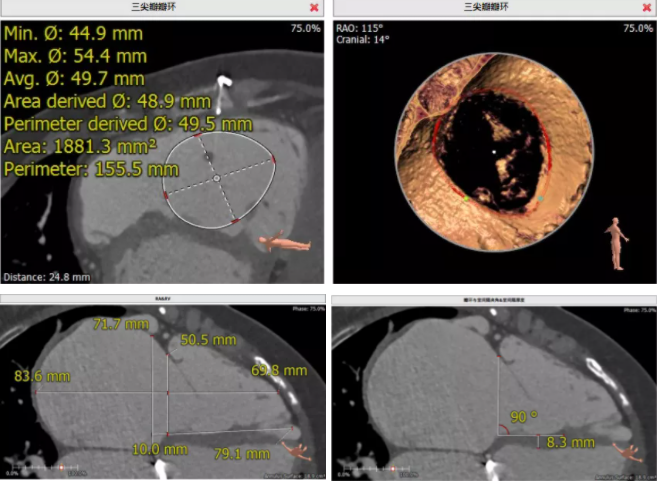

患者為68歲女性,14年前因“反復(fù)感冒、氣促”,檢查發(fā)現(xiàn)心臟瓣膜病,接受了“二尖瓣機(jī)械瓣置換術(shù)”。約5年前出現(xiàn)雙下肢水腫,活動后心累氣緊,心臟彩超提示:三尖瓣返流。近年來三尖瓣返流逐漸加重并伴有輕微黃疸、雙下肢水腫,雖長期服用利尿劑治療,但效果欠佳。郭惠明教授團(tuán)隊(duì)結(jié)合病史、超聲及CT評估,考慮患者瓣膜置換術(shù)后,三尖瓣重度返流,再次開胸行體外循環(huán)手術(shù)風(fēng)險(xiǎn)高,經(jīng)團(tuán)隊(duì)整體評估,決定采用最適合患者的LuX-Valve三尖瓣置換系統(tǒng)行微創(chuàng)治療,根據(jù)測量結(jié)果選擇植入JS/TTVI-28-55型號的LuX-Valve瓣膜。